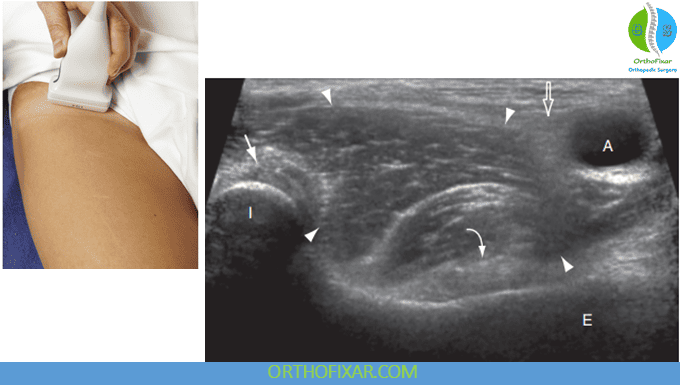

Examination of the lateral hip focuses on the abductor tendons and the greater trochanter area—common sites of gluteal tendinopathy.

- Position the patient on the opposite (contralateral) hip.

- Place the transducer over the lateral hip in the short axis to locate the greater trochanter.

At the apex of the trochanter, two important facets can be identified:

- Anterior facet → attachment of the gluteus minimus

- Lateral facet → attachment of the gluteus medius

Rotating the probe 90° into the long axis allows clear visualization of:

- Gluteus medius tendon (lateral facet)

- Gluteus minimus tendon (anterior facet)

Both structures should appear as hyperechoic tendons inserting into the greater trochanter.

This region is crucial in diagnosing greater trochanteric pain syndrome (GTPS).